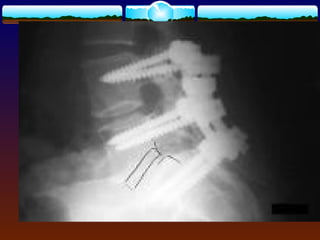

OPERATIVE TREATMENT  Decompressionof neural element  Stabilization of unstable segment

FUSION  Sagittal instability Scoliosis  Iatrogenic pars defect  Greater than 50% facet joint resection